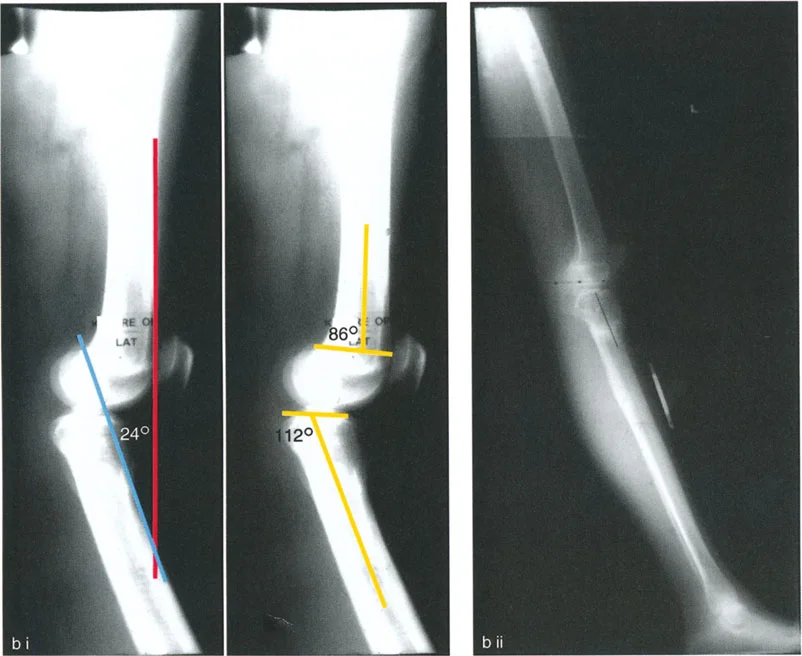

- تقييم مدى الحركة: يتم قياس مدى حركة الركبة، بما في ذلك أقصى تمدد وأقصى انثناء. يتم تحديد درجة فرط التمدد (HE - Hyperextension) أو درجة تقلص الانثناء الثابت (FFD - Fixed Flexion Deformity).

زوايا القياس الهامة:

- زاوية الانحناء البعيدة للفخذ (PDFA - Posterior Distal Femoral Angle): تقيس زاوية الجزء السفلي من عظم الفخذ. القيمة الطبيعية حوالي 84 درجة. الزيادة في هذه الزاوية (أكثر من 84 درجة) تشير إلى ارتداد فخذي.

- زاوية الانحناء القريبة للظنبوب (PPTA - Proximal Posterior Tibial Angle): تقيس زاوية الجزء العلوي من عظم الساق. القيمة الطبيعية حوالي 80 درجة. الزيادة في هذه الزاوية (أكثر من 80 درجة) تشير إلى ارتداد ظنبوبي.

- مركز دوران الزاوية (CORA - Center of Rotation of Angulation): يتم تحديد هذا النقطة على الأشعة السينية لتحديد مكان التشوه العظمي بدقة، وهو أمر بالغ الأهمية لتخطيط عملية قطع العظم.

تحليل الحالات المختلفة:

- الركبة الارتدادية بسبب الارتداد الظنبوبي:

- إذا كانت درجة فرط التمدد (HE) تساوي درجة الارتداد الظنبوبي (PPTA > 80°)، فهذا يعني أن التشوه كله ناتج عن عظم الساق.

- في هذه الحالة، يكون مركز CORA في الجزء القريب من عظم الساق.

أ. قطع العظم الفخذي لتصحيح الارتداد الفخذي:

- متى يتم إجراؤها: عندما يكون التشوه الرئيسي في عظم الفخذ البعيد.

- الإجراء: يتم إجراء قطع للعظم (عادة قطع عظم انثناء) في الجزء البعيد من عظم الفخذ، عند مركز دوران الزاوية (CORA)، لإعادة محاذاة العظم.

- الهدف: تصحيح فرط تمدد الركبة واستعادة المحاذاة الطبيعية.

- مثال: لتصحيح ارتداد فخذي بمقدار 20 درجة، يتم إجراء قطع عظم انثناء فخذي بمقدار 20 درجة.